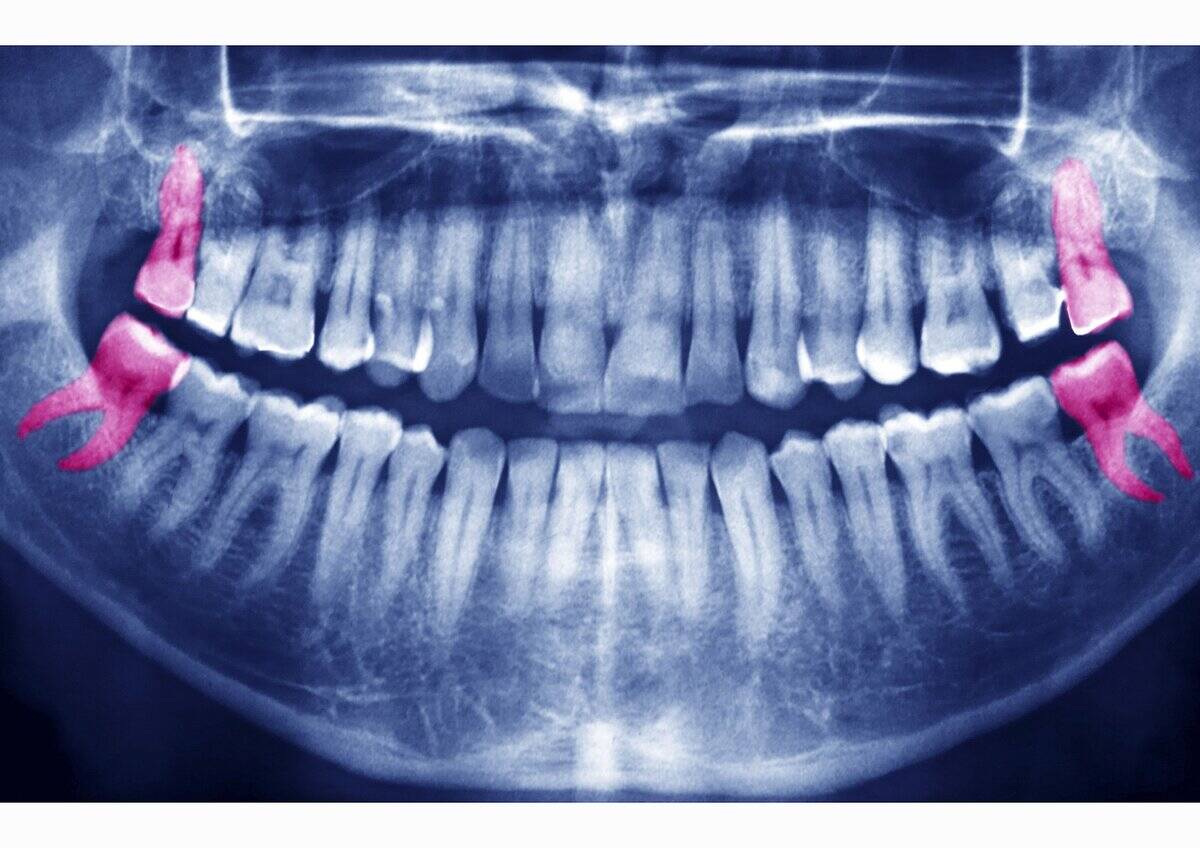

The Evolutionary Quirk of Wisdom Teeth

Wisdom teeth are a relic of our evolutionary past, when our ancestors needed extra molars to chew a diet of raw plants and meat. As human diets and jaw sizes have evolved, these third molars have become largely unnecessary and often problematic.

Many people need them removed due to crowding or improper eruption. Though they no longer serve a critical function, wisdom teeth offer a fascinating glimpse into our evolutionary history.